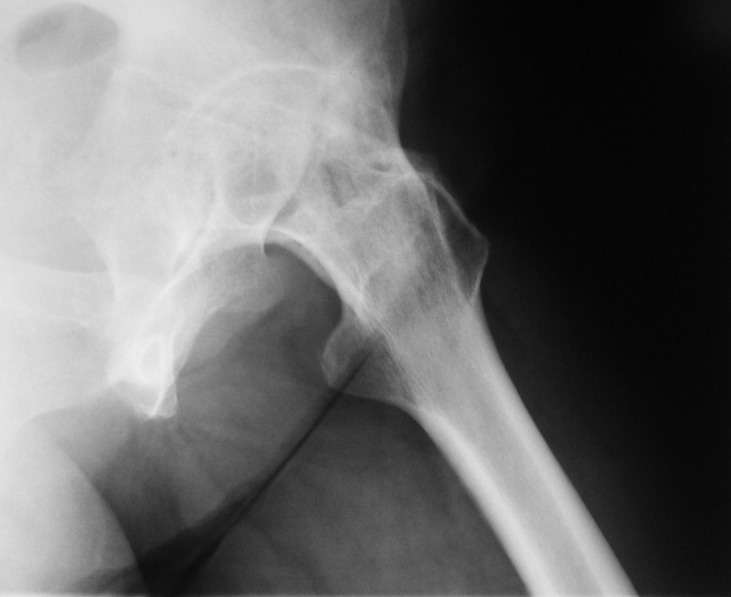

При обследовании выявлен анкилоз тазобедренного сустава в приведении. Видимо, в период пребывания в тяжелом состоянии появились гетеротопические оссификаты. За исключением того, что осталась одна почка, сейчас других медицинских проблем нет.

Пациентку в первую очередь беспокоят боли в спине, на отсутствие движений в суставе она вроде и не жалуется. Вопрос насчет тактики. Корсет и анальгетики вряд ли решение. Первый вариант - удаление оссификатов и эндпротезирование, второй - корригирующая остеотомия в проксимальном отделе с устранением порочного положения.

Второй вариант много проще и менее травматичен. Можно ли без размыкания сустава рассчитывать на существенное уменьшение боли за счет устранения перекоса таза?

Боли в спине обусловлены порочным положением бедра. Эндопротезирование более интересно, т.к. дает еще и движения в суставе (кроме устранения порочного положения). Оссификаты не страшные, а учитывая срок (3 года) - уже созревшие. Я зарекся делать ЭТС при больших оссификатах - очень частый рецидив даже на фоне индометацина и луч.терапии.

Я думаю, что эндопротезирование - более предпочтительный вариант у пациентки 53 лет. К тому же суставная щель прослеживается и, вероятнее, большой сложности с установкой вертлужного компонента не будет. Высока вероятность необходимости аддуктотомии.

В любом случае замена сустава после оссификации дело не благодарное - безболезненная контрактура станет болезненной контрактурой.